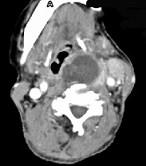

问题 女,64岁,双甲状腺占位40余天。如图所示甲状腺病灶应诊断为()

选项 A.结节性甲状腺肿 B.甲状腺腺瘤 C.甲状腺癌并淋巴结转移 D.甲状腺转移瘤 E.甲状腺结核

答案 C